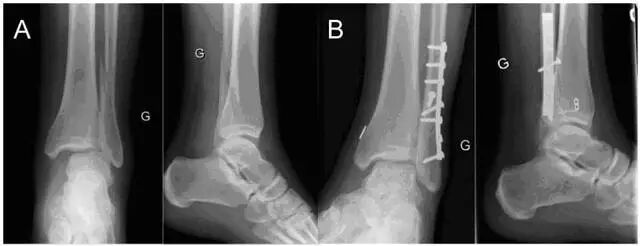

图 2  使用带袢纽扣钢板固定下胫腓联合损伤示意图。A 一例典型的 Weber C 型骨折;B 开放复位并使用带袢纽扣钢板固定术后踝关节正侧位片(图片来自文献 [7])

除了使用金属螺钉和可吸收螺钉牢固固定,还可弹性固定下胫腓联合,包括使用缝线进行纽扣缝合、使用缝合锚或带袢纽扣钢板进行弹性固定等,临床最常用的固定方式为带袢纽扣钢板固定。

弹性固定可在固定下胫腓联合的同时,保持了其微动功能,以利于踝关节功能恢复,避免拉力螺钉松动、断裂及二次手术。

Kortekangas 等 [6] 和 Laflamme 等 [7] 的研究发现,使用带袢纽扣钢板固定下胫腓联合的患者二次手术率显著低于使用下胫腓联合螺钉的患者,且功能预后无明显差异,可以成为一个替代选择。